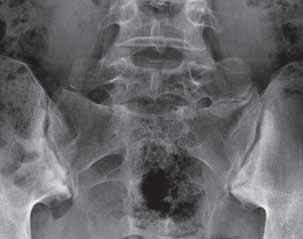

Nadżerki – na wstępnym etapie ich powstawania manifestują się na radiogramach odcinkowym zatarciem zarysu warstwy korowej. Wykształcona nadżerka jest ubytkiem cieniowym warstwy podchrzęstnej z przerwaną ciągłością warstwy korowej oraz sklerotycznymi zarysami (reactive sclerosis), pojawiającymi się wraz z czasem trwania choroby. Zachowanie warstwy korowej przemawia za geodą, czyli torbielą zapalną, która jest obszarem nacieku zapalnego i niszczenia warstwy podchrzęstnej tkanki kostnej, o kształcie zazwyczaj okrągłym. Jest widoczna w RTG jako przejaśnienie, początkowo o nieostrych zarysach, w stanach przewlekłych z odczynową sklerotyzacją brzegów. Należy ją różnicować z torbielą zwyrodnieniową, która zazwyczaj jest większa i ma sklerotyczną otoczkę (decyduje całość obrazu RTG).

Nadżerki mogą występować w stawach obwodowych, krzyżowo-biodrowych, w kręgosłupie, w miej-

scach przyczepów ścięgien, więzadeł i torebki stawowej, czyli w entezach – typowo w przebiegu spondyloartropatii zapalnych.

W stawach obwodowych wyróżnia się tzw. nadżerki brzeżne (najczęściej w przebiegu RZS, ŁZS i ReZS), zlokalizowane między granicą chrząstki szklistej a przyczepem torebki stawowej, tj. w miejscu bezpośredniego kontaktu zmienionej zapalnie błony maziowej z kością) oraz nadżerki podchrzęstne, widoczne po zniszczeniu chrząstki szklistej. Nadżerki tworzą się także w procesie ewolucji geody, która powstaje wskutek uwalniania cytokin prozapalnych przez nacieki komórkowe w szpiku kostnym i po przerwaniu warstwy korowej staje się nadżerką. Zwiększająca się wraz z postępem choroby wielkość i liczba nadżerek prowadzą do destrukcji powierzchni stawowych, aż do całkowitego zaniku szpary stawowej, następnie zesztywnień włóknistych i kostnych oraz do deformacji stawu.